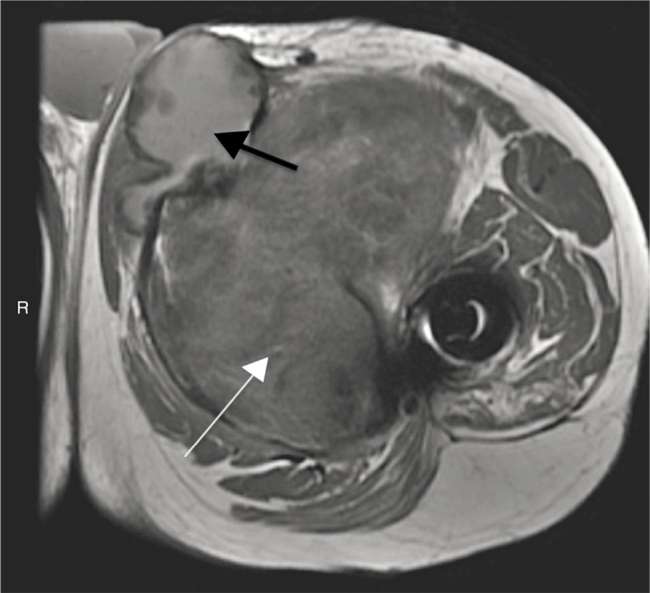

Fig. 2.

MRI axial view of the proximal region of the left thigh weighted in T1. White arrow, hyposignal and expansive formation in muscle planes in the anteromedial region of the left thigh. Black arrow, adjacent cyst with presence of fluid collection and thick content and debris inside.